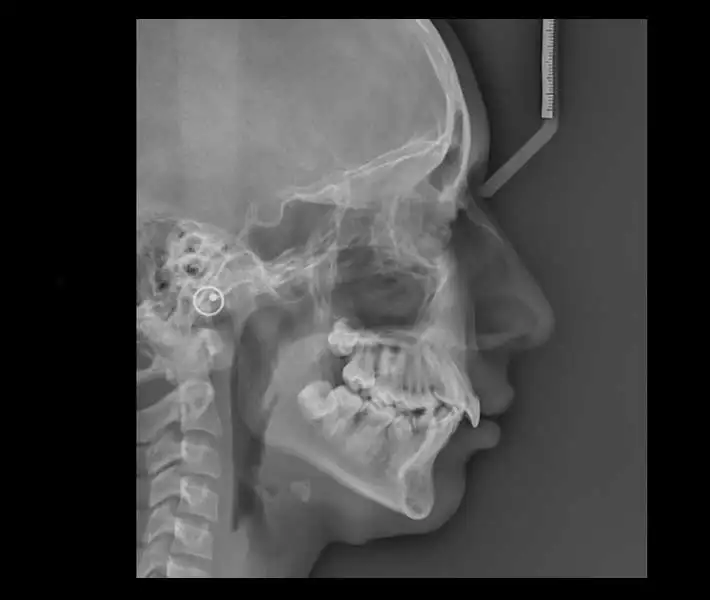

- رادیوگرافی لترال سفالومتری وسایر رادیوگرافیهای جمجمه